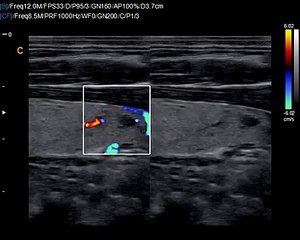

Q5 by Chison imaging Fetal Heart sonogram, easy to see heart in fetus, neonatal ultrasound